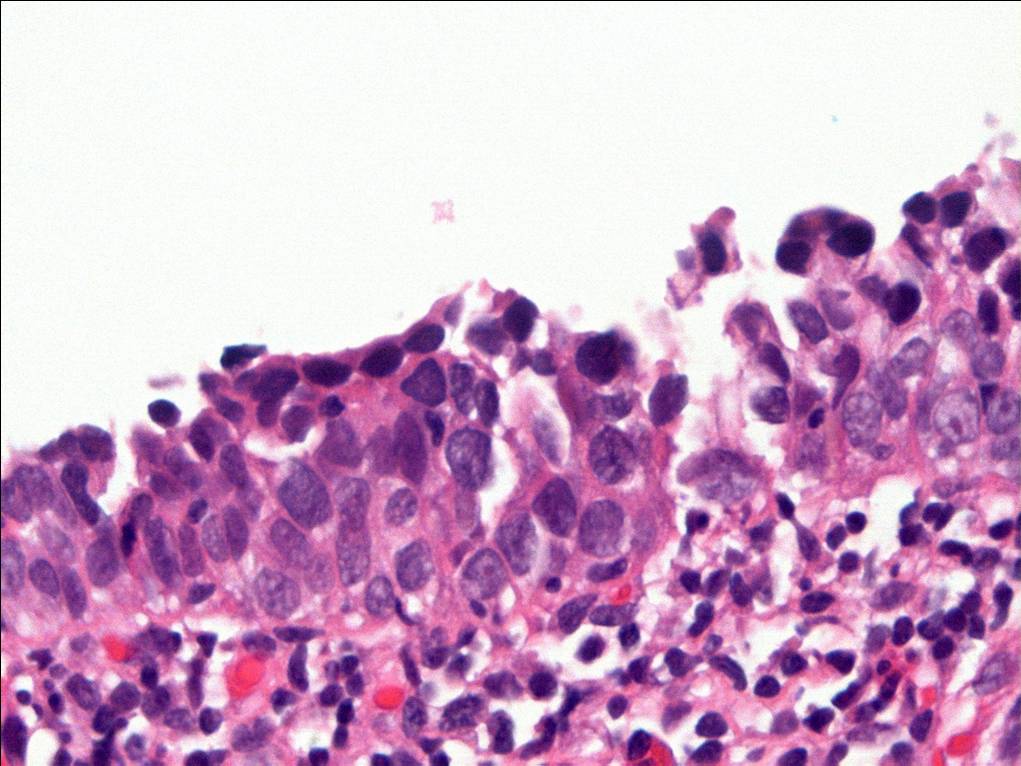

Consensus grade: Carcinoma in situ (CIS)

Some of the atypical urothelial cells present have high nuclear:cytoplasmic ratio raising the possibility of at least some element of so-called 'small cell' urohtlelial CIS (not meant to imply neuroendocrine differentiation). |

Case description (by case creator):

The degree of cytologic atypia and loss of polarity is disproportionate to the inflammation present in the lamina propria and the degree of atypia is greater than would be acceptable for reactive atypia.